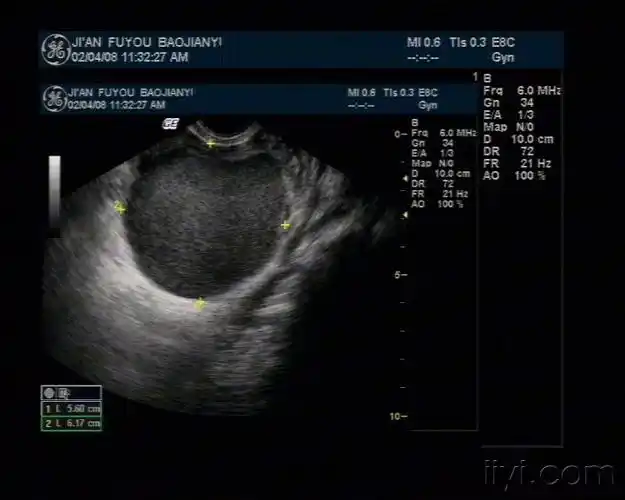

典型的巧克力囊肿 - 超声医学讨论版 - 爱爱医医学论坛